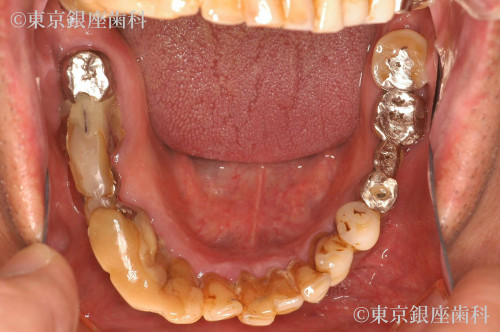

昔行ったインプラントからワンデイインプラントに変更

歯周病が進行したため、上下でワンデイインプラントを実施